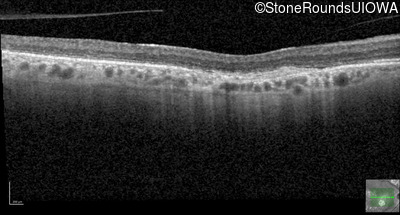

Optical Coherence Tomography - Left - 20/100

Exemplar / OCT Stack